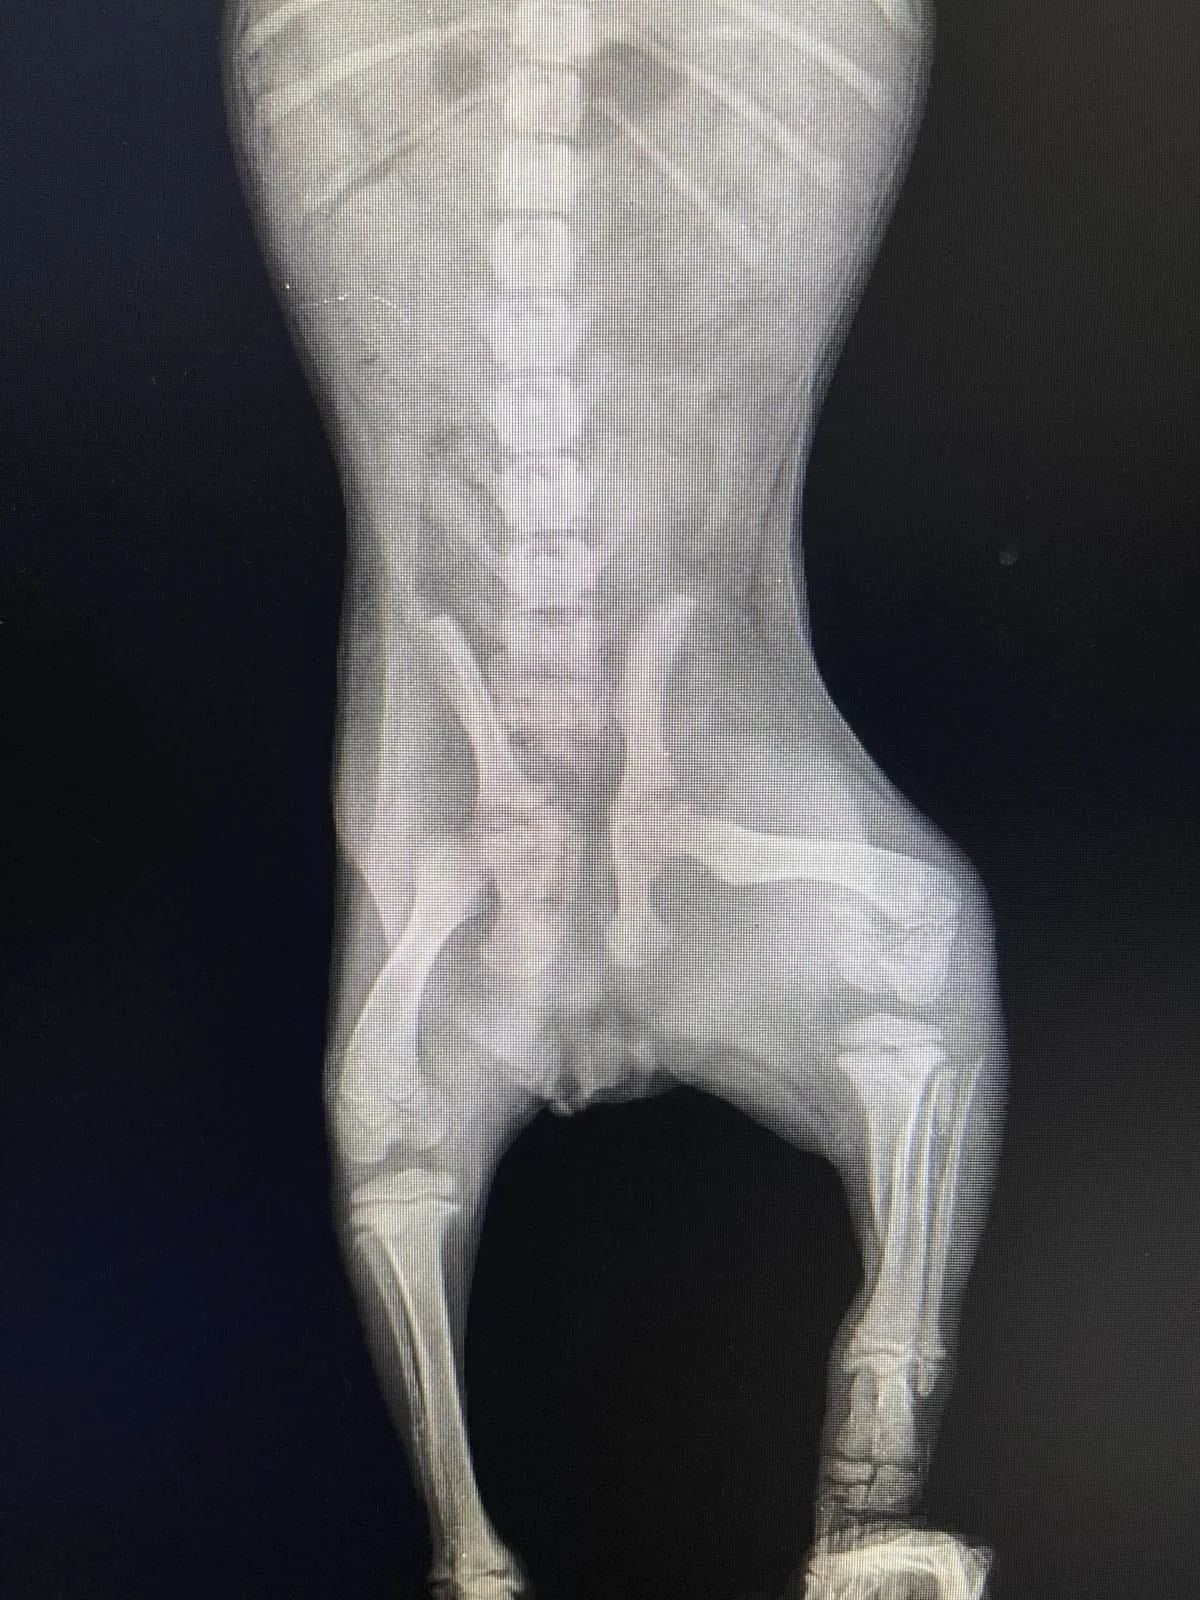

Röntgen foto's laten 3 breuken zien. Ze gaan aan twee opereren en de derde zou even moeten wachten.

Bij de dierenarts bleek dat haar dijbeen te zijn gebroken.

Het is dringend om rontgenfoto 's te maken en zo snel mogelijk te opereren